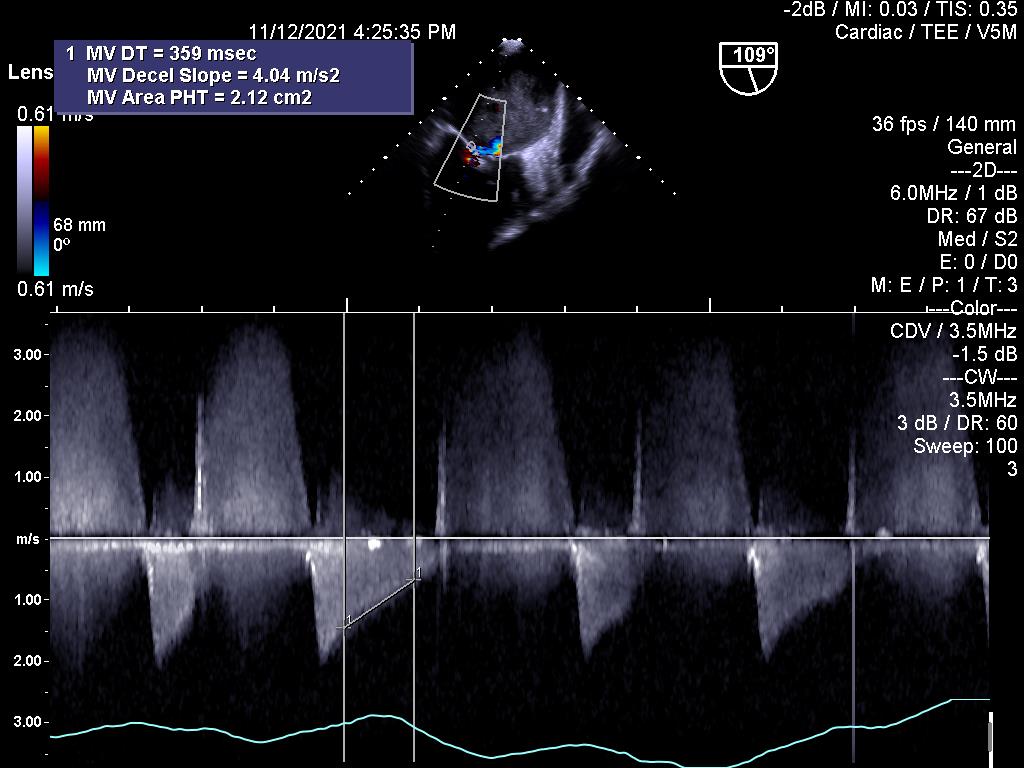

1.Huyết khối gây kẹt van hai lá cơ học:

2.Đánh giá hiệu quả điều trị bằng thuốc tiêu sợi huyết đối với kẹt van cơ học (cùng bệnh nhân ở trên)